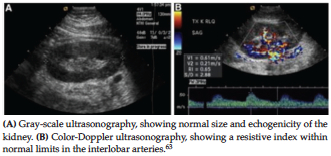

Conventional grayscale ultrasonography with color and spectral Doppler is used immediately posttransplant for early detection of complications and evaluation of the renal allograft; it also allows calculation of resistive index and pulsatile index, which may predict early and longterm outcomes of noncomplicated renal transplants (Figure 1).7,36,37-41 It is noninvasive and is an easily available tool that avoids use of ionizing radiation and iodinated contrast media. It is generally considered safe in the hands of a trained and skilled operator.31

Conventional grayscale ultrasonography has limited application, especially with increasing renal volume and a dark/edematous cortex in the early phase, transitioning to a smaller kidney with echo­genic cortex as the disease progresses. Because the vascular anastomoses are deep in the recipient’s pelvis, thrombus in the renal vein is rarely seen on conventional ultrasonographic imaging.40